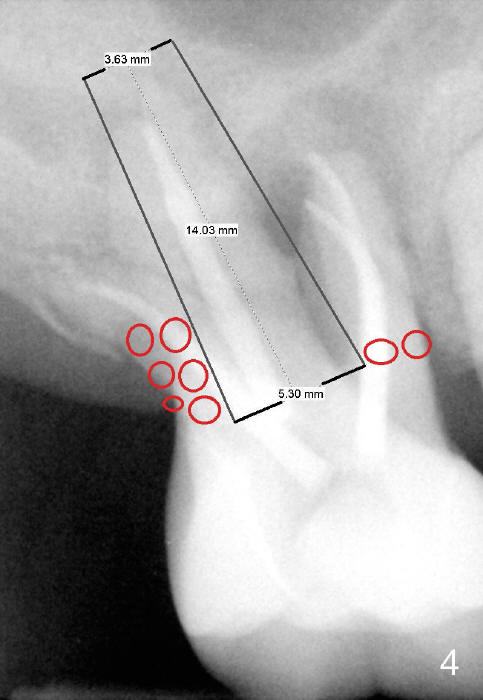

If the septum is basically intact, a 5.3x12 bone-level implant is placed in an ideal trajectory for restoration (Fig.3). The mesial and distal margin of the implant is at the level of the alveolar crests (arrows); bone graft is placed evenly to cover the coronal threads (red circles). If the septum is defective to some degree, a longer implant is placed distally (Fig.4) with more bone graft placed distally. Or the implant is placed deeper (Fig.5). If the septum is severely defective, an extra wide, but shorter implant (6.9x10 mm bone-level SM) is used (Fig.6). Or an extra wide UF implant with extra 2 mm length may offer better primary stability (Fig.6' (with sinus lift)). The primary stability of the extra wide implants is derived from contact with the mesial and distal socket walls.